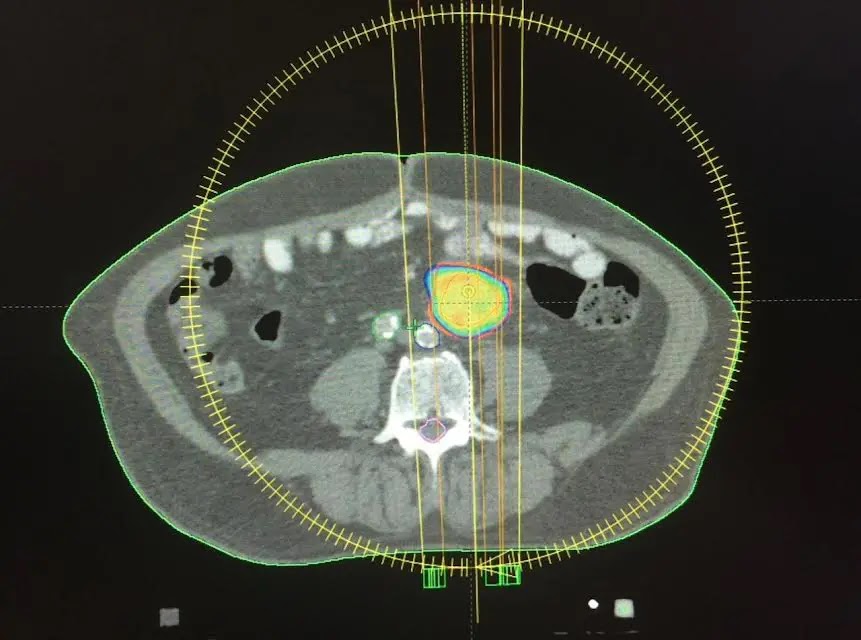

En 2015, especialistas del HOMS practicaron de manera exitosa la primera técnica de radiocirugía extracraneal, con avanzada tecnología en su Centro del Cáncer. La práctica se realizó en un paciente con metástasis ganglionar de primario colorrectal, utilizando PET-CT y tomografía de abdomen y pelvis con doble contraste, fusión de ambas imágenes y posterior verificación antes del tratamiento, mediante imágenes tomográficas del blanco a tratar.